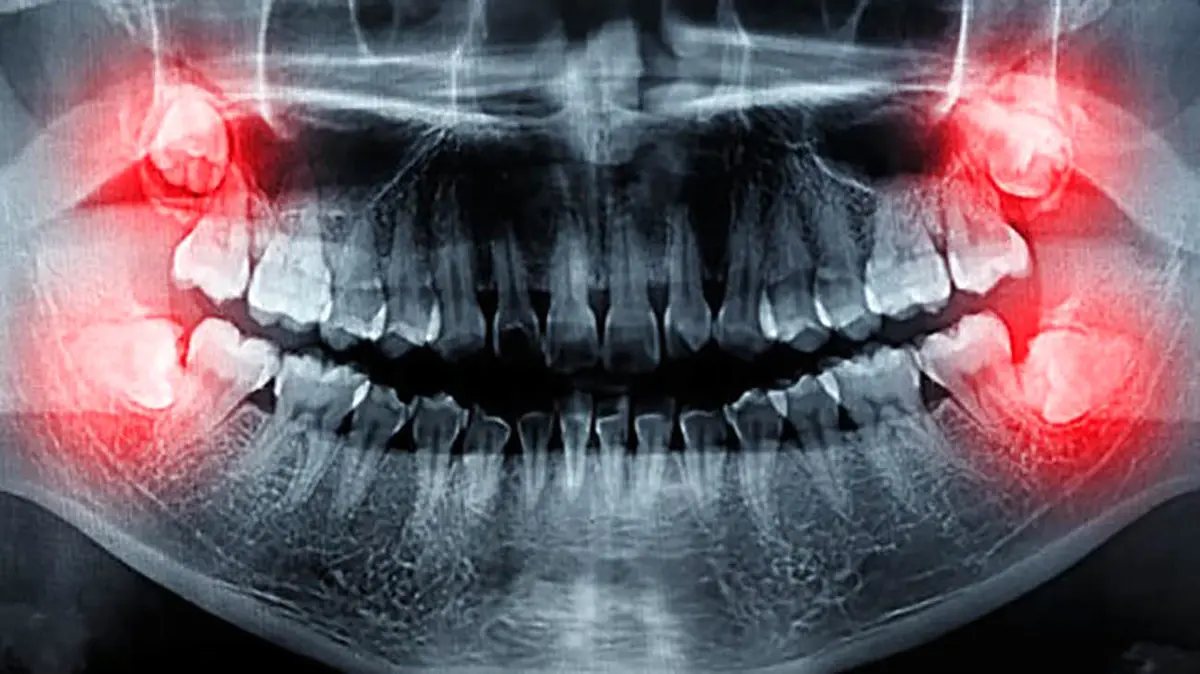

ریشه دندان عقل معمولاً بلندتر از سایر دندانهاست زیرا این دندانها باید به خوبی در استخوان فک قرار گیرند و فشار بیشتری را تحمل کنند. همچنین، این دندانها ممکن است به دلیل فضای محدود در فک، رشد نامنظم و پیچیدهای داشته باشند.

عوامل مختلفی ممکن است باعث درد در دندان عقل شوند. اگر فضای کافی برای رشد وجود نداشته باشد، به سایر دندان ها فشار زیادی وارد می شود و درد در دندان عقل ایجاد می کند. عفونتهای باکتریایی در ناحیه لثه و التهاب ناشی از رشد دندان ایجاد کننده درد در دندان عقل هستند. پوسیدگی دندان به دلیل عدم دسترسی مناسب برای تمیز کردن یکی دیگر از عوامل به وجود آورنده درد در دندان عقل است.

برای پیشگیری و درمان درد دندان عقل، روش های مختلفی وجود دارد. بررسی وضعیت دندانهای عقل با عکسبرداری، رعایت بهداشت دهان برای جلوگیری از عفونت و پوسیدگی ، مصرف داروهای مسکن برای کاهش درد و جراحی و کشیدن دندان عقل تحت نظر دندانپزشک از جمله راه های پیشگیری و درمان درد درمان عقل است.